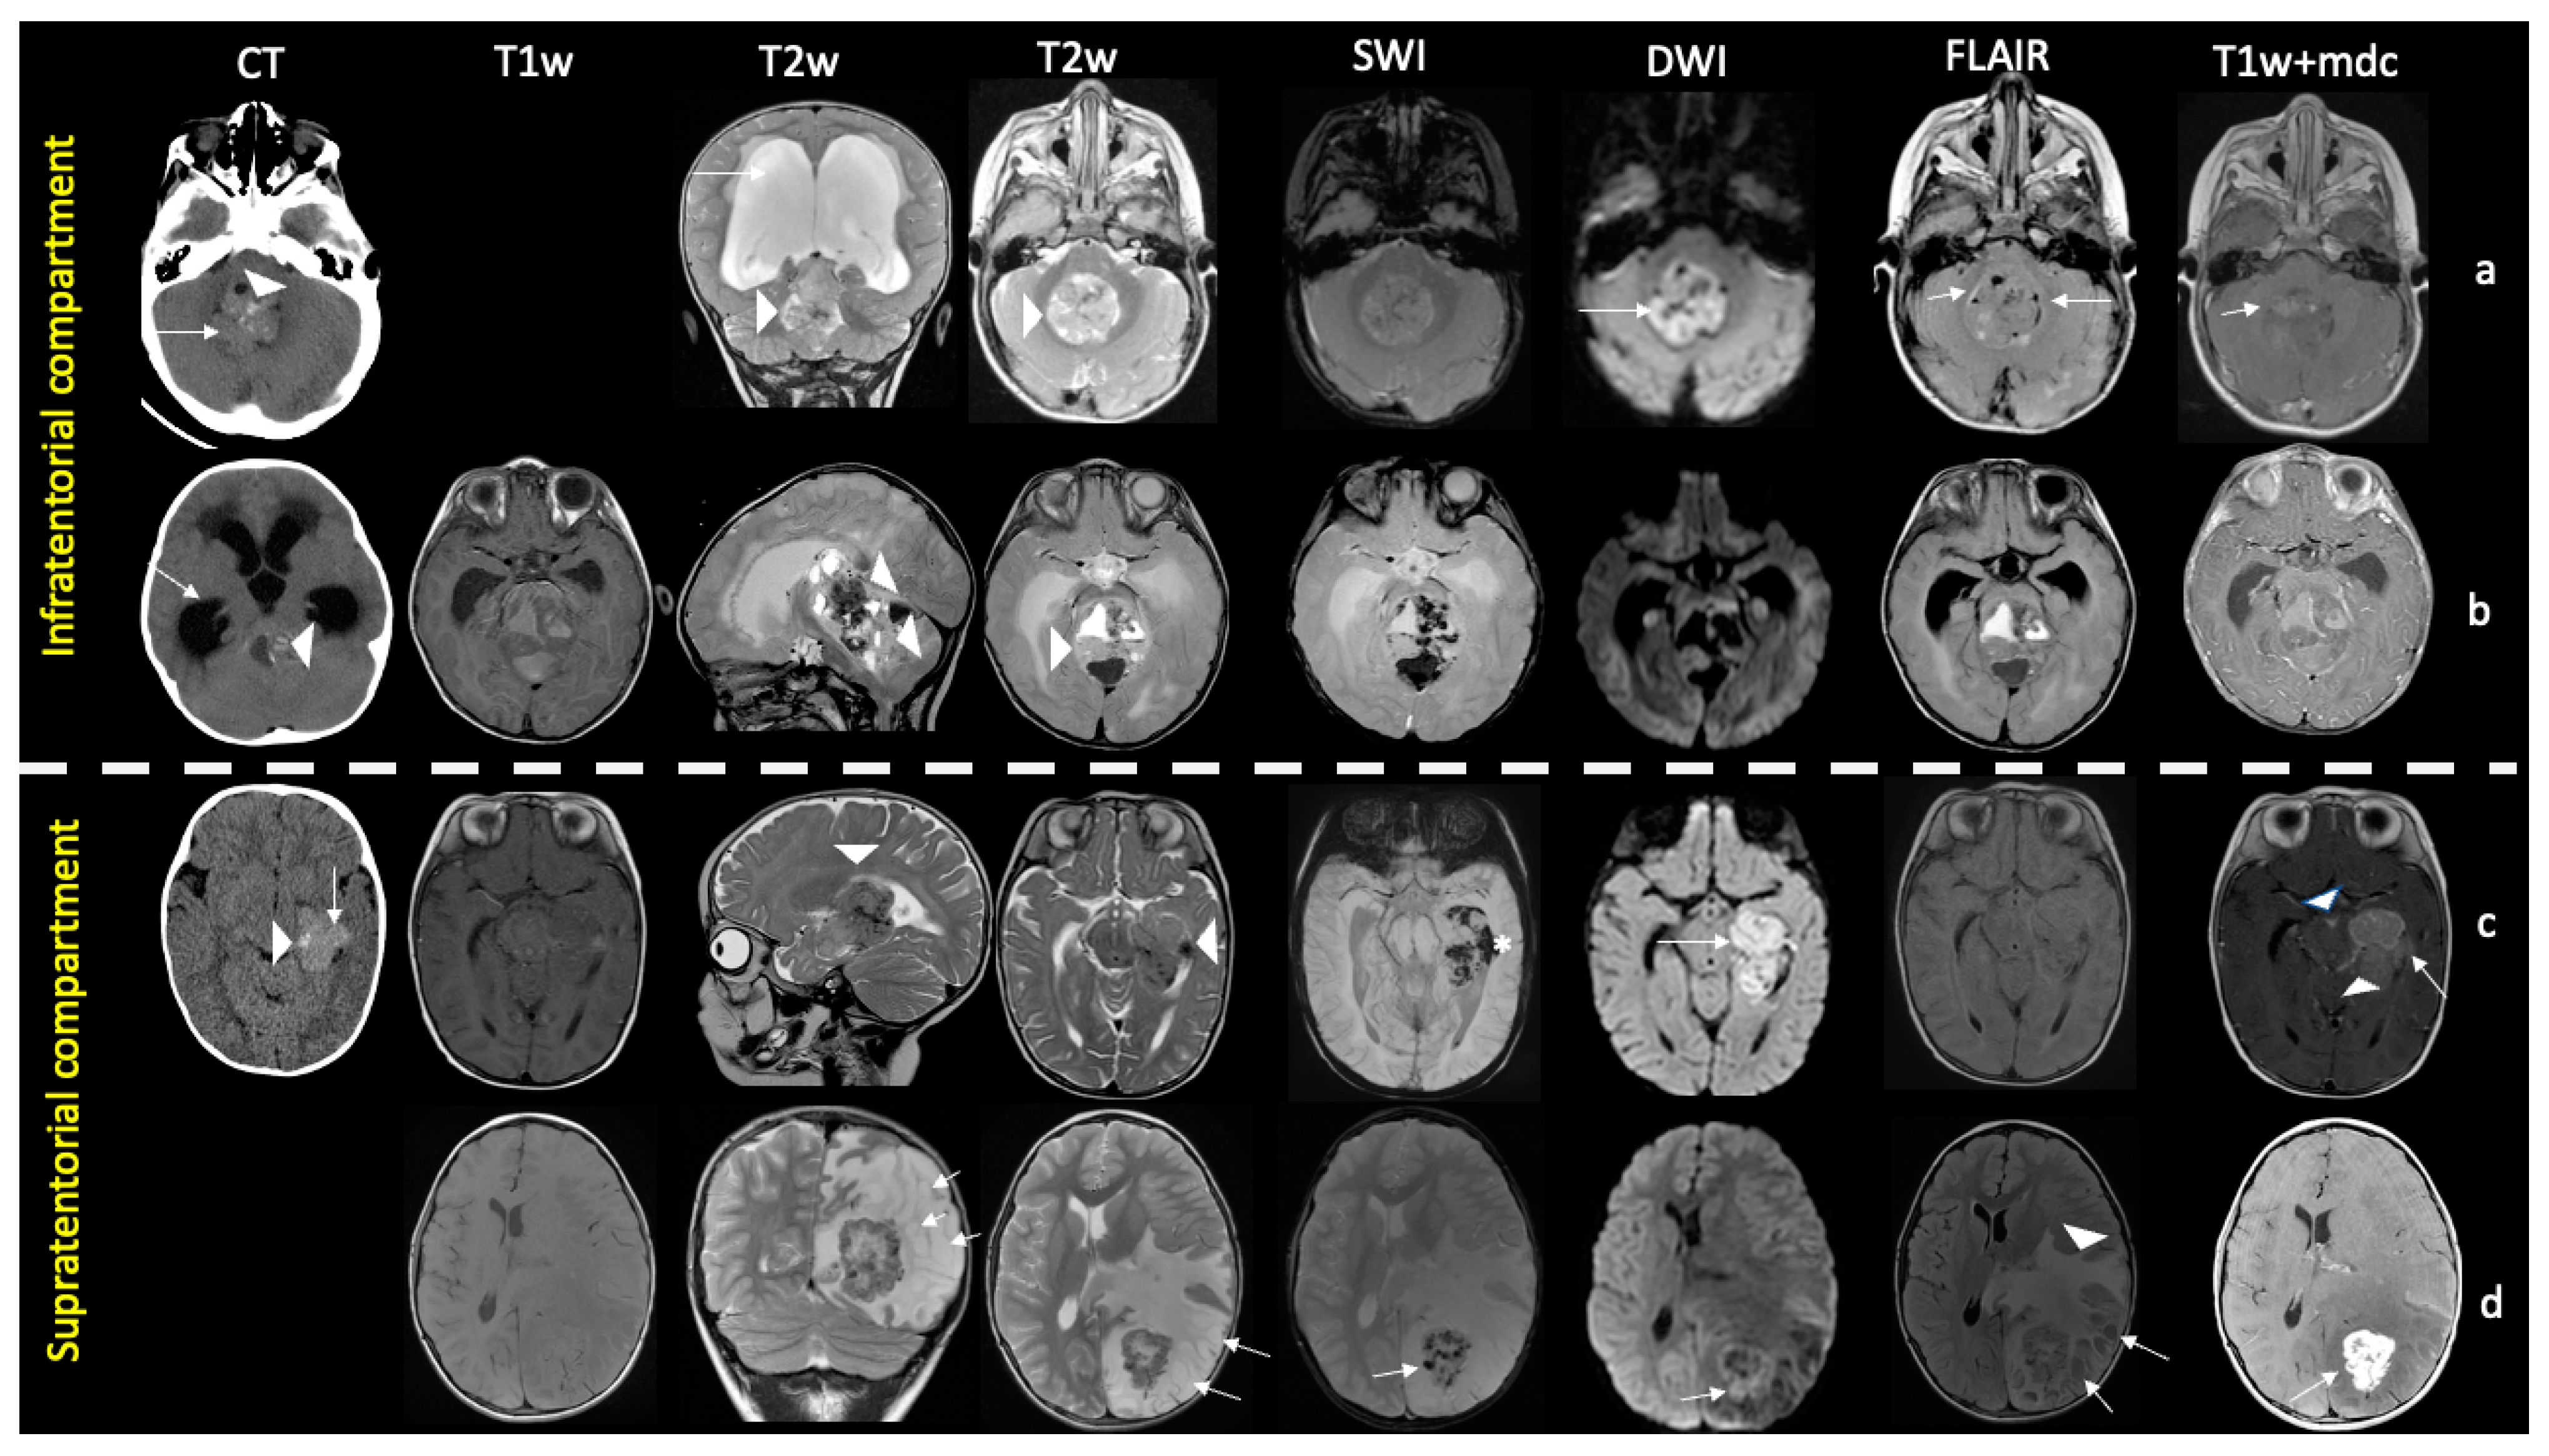

ATRTs in pediatric patients were large at the diagnosis (average 50 × 40.3 mm). Four tumors were predominantly solid (two in posterior cranial fossa, one in temporal lobe, one in fronto-temporal lobes), while six were heterogeneous tumors with solid and cystic components. Almost all cysts were peripherally located and more frequent in the supratentorial compartment, five of our cases (50%) had calcifications, and four (40%) had intratumoral hemorrhage. Perifocal edema varied but was more frequent in the supratentorial compartment than in the infratentorial compartment, ranging from minimum to extensive. The solid part of these tumors showed restricted diffusion compared with normal brain parenchyma in nine patients, (hyperintensity on DWI and hypo-intensity in ADC), indicating high cellularity of the tumor. Contrast enhancement was noted in nine patients (one supratentorial tumor showed a “wavy” bandlike pattern) while in only one patient, tumor in PCF did not show any enhancement (Figure 2).

Figure 2.

Imaging findings of pediatric ATRT in supra- and infratentorial compartments. Infratentorial ATRTs (rows (a,b)). Row (a): One-year-old child with a prevalently solid mass centered in the IV ventricle, hyperintense to gray matter (arrowheads in T2w) with high density/restricted diffusion (arrows in CT, DWI) due to hypercellularity, minute eccentric cystic components (arrows in FLAIR), and mild enhancement (arrow in T1+mdc). Intratumoral foci of Ca++ (arrowhead in CT) are present, interstitial edema is absent. Hydrocephalus is shown (white arrow in T2). Row (b): a 4-month-old child with a bulky heterogeneous mix mass with epicenter in the posterior cranial fossa (IV ventricle and vermis) and supratentorial extension (arrowheads in T2w). The lesion contains small hyperdense foci of Ca++ (arrowhead in CT), hemorrhage both in solid and cystic component (hyperintense signal in T1w, hyperintense and hypointense signal in T2w, hypointense signal in SWI). Interstitial edema is absent. Hydrocephalus is detected (white arrow in CT). Supratentorial ATRTs (rows (c,d)). Row (c): a 7-month-old child with a solid and heterogeneous intracranial mass centered in the temporal lobe, near to lateral ventricle (arrowheads in T2w). It shows high density (arrow in CT) and restricted diffusivity (arrow in DWI) due to hypercellularity, containing foci of Ca++ (arrowhead in CT), areas of hemorrhage (* in SWI), and marked enhancement (arrow in T1+mdc). Note widespread subarachnoid metastatic disease filling the interpeduncular and perimesencephalic cisterns (arrowheads in T1+mdc). Row (d): a 10-year-old child with a mixed lesion in the parietal lobe consisting of a heterogeneous solid component due to hypercellular (arrow in DWI) and hemorrhagic areas (arrow in SWI) and multiple eccentric cysts (arrows in T2 and FLAIR); note marked enhancement (arrow in T1+mdc) of the solid component and abundant perimarginal edema (arrowhead in FLAIR).